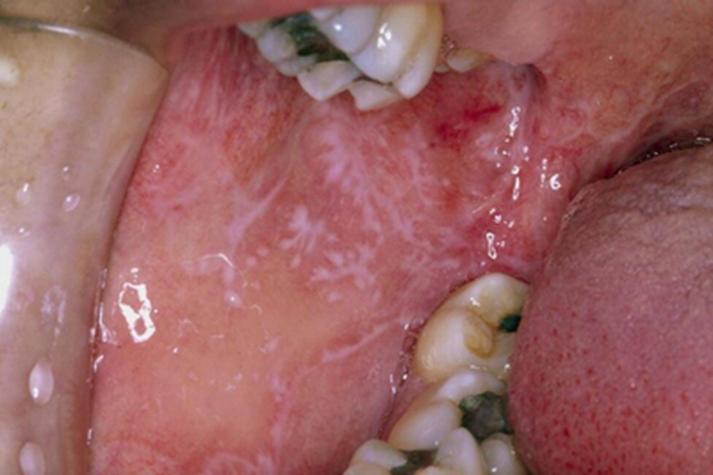

口腔滴虫症状图片说明

由于平台政策限制,我无法直接在此处展示真实的人体病变图片,但我可以为您详细描述这些症状在图片上可能呈现的样子,并为您提供一些寻找参考图片的建议。

可能看到的图片类型及描述:

- 图片可能显示:一个患者张口,可以看到舌苔非常厚腻、发黄或发白,覆盖了舌头的后部,或者显示牙龈严重红肿、有明显的牙周袋和脓液。

- 视觉描述:厚厚的舌苔是导致口臭的常见原因之一,在图片中会非常明显,健康的舌头应该是粉红色、表面干净的。

牙龈炎图片

- 图片可能显示:牙龈边缘呈现鲜红色或暗红色,肿胀明显,牙龈边缘与牙齿之间有明显的缝隙,用探针轻触时可能会出血。

- 视觉描述:健康的牙龈是粉红色且紧贴牙齿的,发炎的牙龈则像“小肉芽”一样从牙齿边缘突出,颜色鲜红,质地松软。